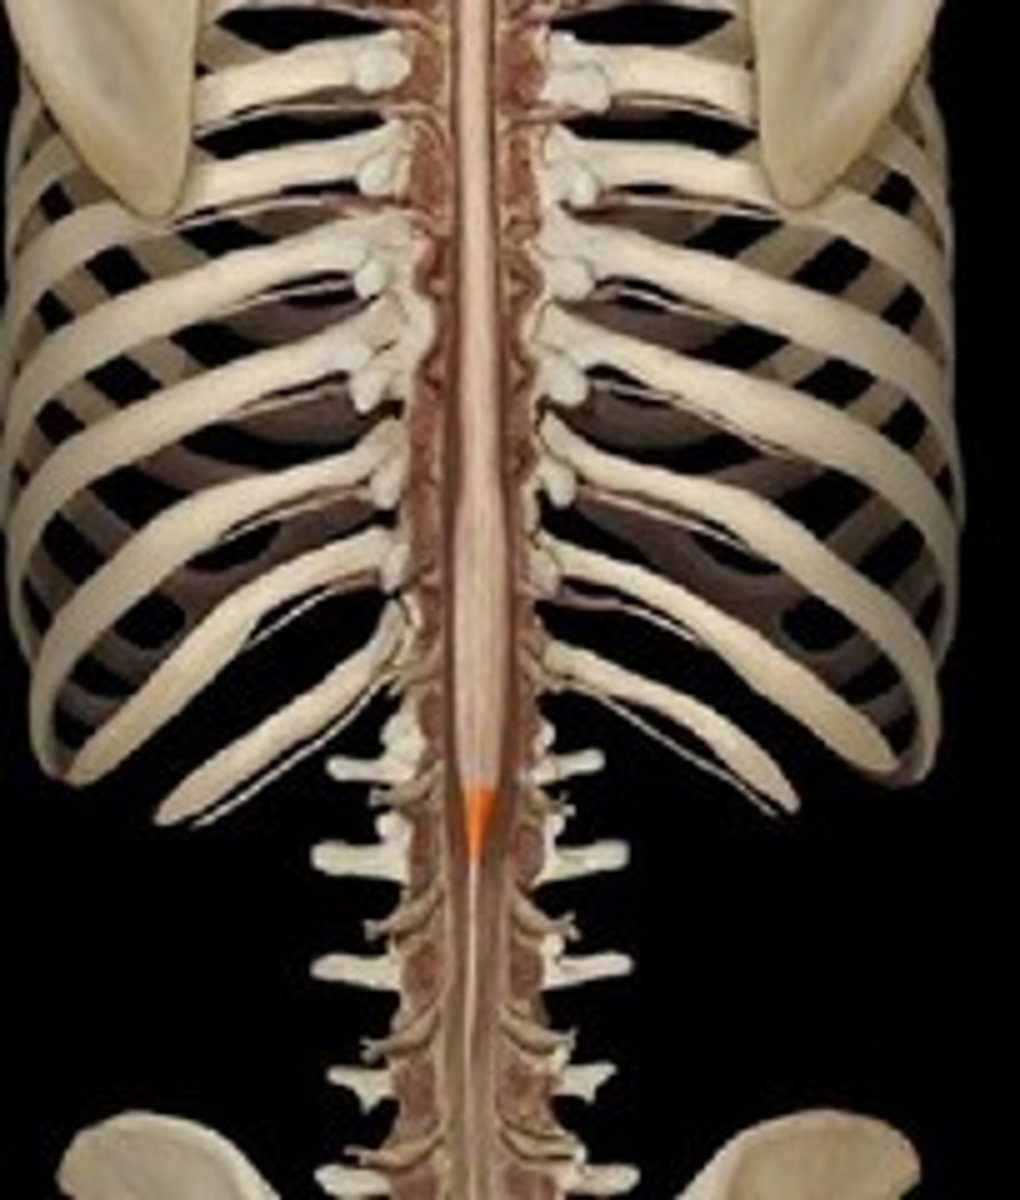

conus medullaris

L1/L2

what level is the conus medullaris located

what level does spinal cord end

condus medullaris

what is the name of where the spinal cord ends

L1-L2

what vertebra is the condus medullarius located